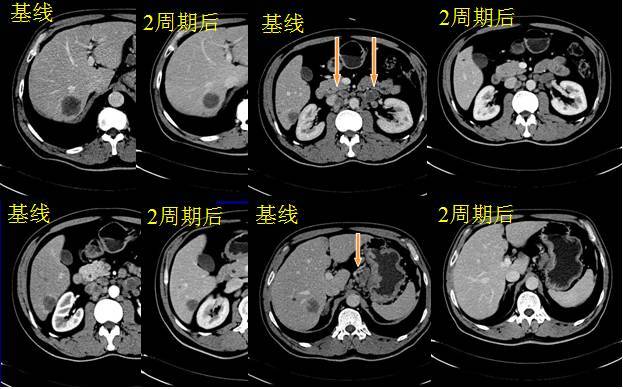

2009年12月至2010年05月行第1-8周期“曲妥珠单抗(赫赛汀)+DCF”方案(每3周)一线化疗联合靶向, 由于FISH检测时间长,开始两周期给予单纯化疗,具体用药:多西他赛,100mg,静滴,d1;注射用顺铂,100mg,静滴,d1;氟尿嘧啶,750mg,滴斗入,d1、2,3000mg,泵入,48h;亚叶酸钙,300mg,静滴,d1、2。2周期后复查腹部CT结果提示肝转移及腹腔淋巴结较前缩小,疗效评价MR。

2周期后复查CT

第三周期加用曲妥珠单抗,440mg,静滴,d0;4周期后复查疗效评价PR,6、8周期后复查疗效评价维持PR。